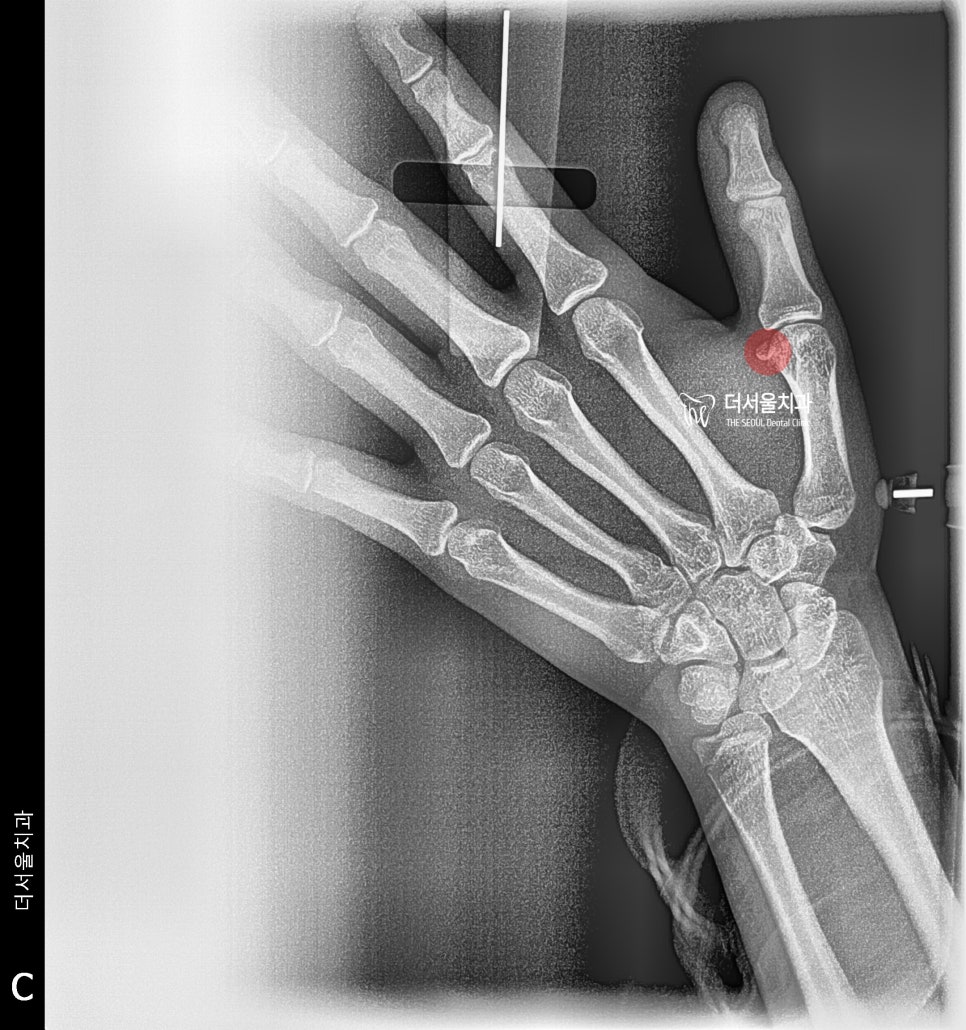

그래서 치료 계획 수립에 앞서,

먼저 성장판 검사를 하게 됩니다.

수완부 촬영인데,

아직 턱이 더 클 수 있다는 것을 뜻합니다.

(종자골이 없음)

성장도 이제 멈추셨습니다.

종자골이 만들어졌기 때문에

아마 턱도 이제는 성장이

턱 교정 에 따른 변화 사진